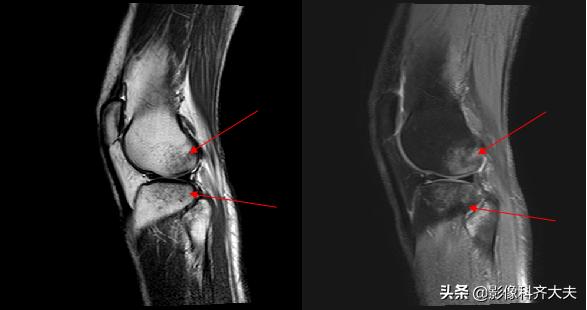

骨挫伤(bone bruise):外力作用引起的骨小梁断裂和骨髓水肿、出血,T1WI低信号,T2WI高信号,压脂序列显示清晰。平片和CT 上常无异常发现。

右胫骨骨挫伤-MRI清晰显示病灶位置

胫腓骨骨挫伤

胫腓骨对应性骨挫伤